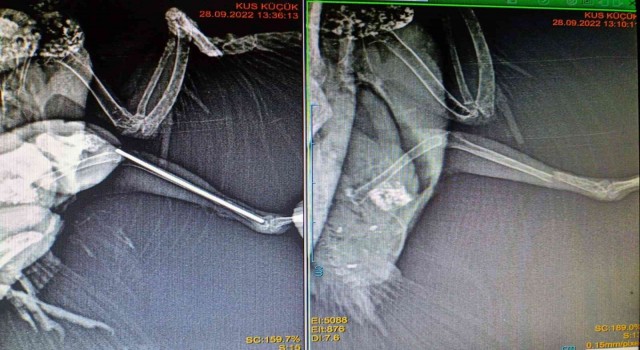

ZONGULDAK’TA AYAĞI KIRILAN ZARİFE İSİMLİ 7 YAŞINDAKİ SULTAN PAPAĞANIN SOL AYAĞINA 0.1 MİLİMLİK PLATİN TAKILARAK TEKRAR YÜRÜMESİ SAĞLANDI.

Zonguldak’ta ayağı kırılan 7 yaşındaki sultan papağanının sol ayağına 0,1 milimlik platin takılarak tekrar yürümesi sağlandı.

Zonguldak’ta Betül Göksel’e ait sultan papağanının sol ayağı kırıldı. Hayvan sahibi Göksel, papağını kent merkezindeki veteriner kliniğine getirdi. Veteriner Hekim Önder Alkan tarafından ameliyata alınan papağana, Türkiye’de nadir gerçekleşen ve sadece gaz anestezisi ve cerrahi mikroskopun gerektiği işlem yapılarak sol ayağına 0,1 milimlik platin takıldı. Ameliyatın ardından sağlığına kavuşan papağanın, yapılacak etkinliklerin ardından tekrar yürümesi planlanıyor.

Veteriner Önder Alkan, “7 yaşında cennet papağını. Ayağını kırmış, alt bacağını kırmış. Maalesef bunu kuşlarda tedavi etmek çok zor. Atele almak çok zor kuşlar orayı kemirdiği için. Bırakıldığı zaman da kuşlar kangren olabiliyor. Çok ince bir ameliyatı var, Türkiye’de nadir yapılan bir ameliyat. Biz merkezimizde bunu yapıyoruz. Bunu yapabilmek için alet gerekiyor. Gaz anestezisi artı mikro cerrahi mikroskop gerekiyor. 0,23 cm kemiğe platin koyuyorsunuz. 0,1 milimlik bir platin koyuyorsunuz. Bu da mikro cerrahi gerekiyor. Bu operasyonu gerçekleştirdik. Betül Göksel’e ait bir hastamız. Bugün ameliyatımızı yapıp taburcu ettik, inşallah düzelecek. 1 hafta sonra kontrollerini yapacağız. Çok ince bir işçilik gerektiği için mikro cerrahi, mikroskop gerektiği için her merkezde bu bulanamıyor. Dolayısıyla nadir yerlerde yapılabiliyor” diye konuştu.